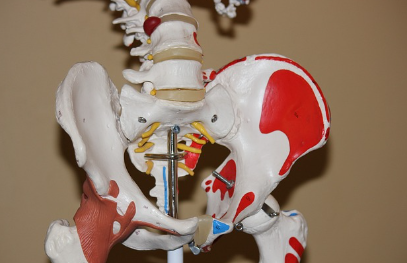

관절의 완충제 역할을 하는 연골을 강화하고, 통증 완화 및 피부 탄력 증진, 안구건조증 개선에도 효과적이라고 알려져 있습니다. 오늘은 특히 콘드로이친 1200mg 복용이 왜 권장되는지, 어떤 효과를 기대할 수 있는지를 자세히 살펴보겠습니다.

콘드로이친은 관절 연골을 구성하는 중요한 성분으로, 관절의 수분 유지와 탄력성을 증가시키는 역할을 합니다. 특히, 콘드로이친 1200mg은 관절 통증과 염증을 감소시키는 데 효과적이며, 장기적인 복용을 통해 관절의 기능을 향상시킬 수 있습니다. 관절염 환자에게 콘드로이친 1200mg 복용은 통증 완화뿐만 아니라 연골의 감소를 억제하고 염증을 줄이는 데 도움을 줄 수 있습니다.